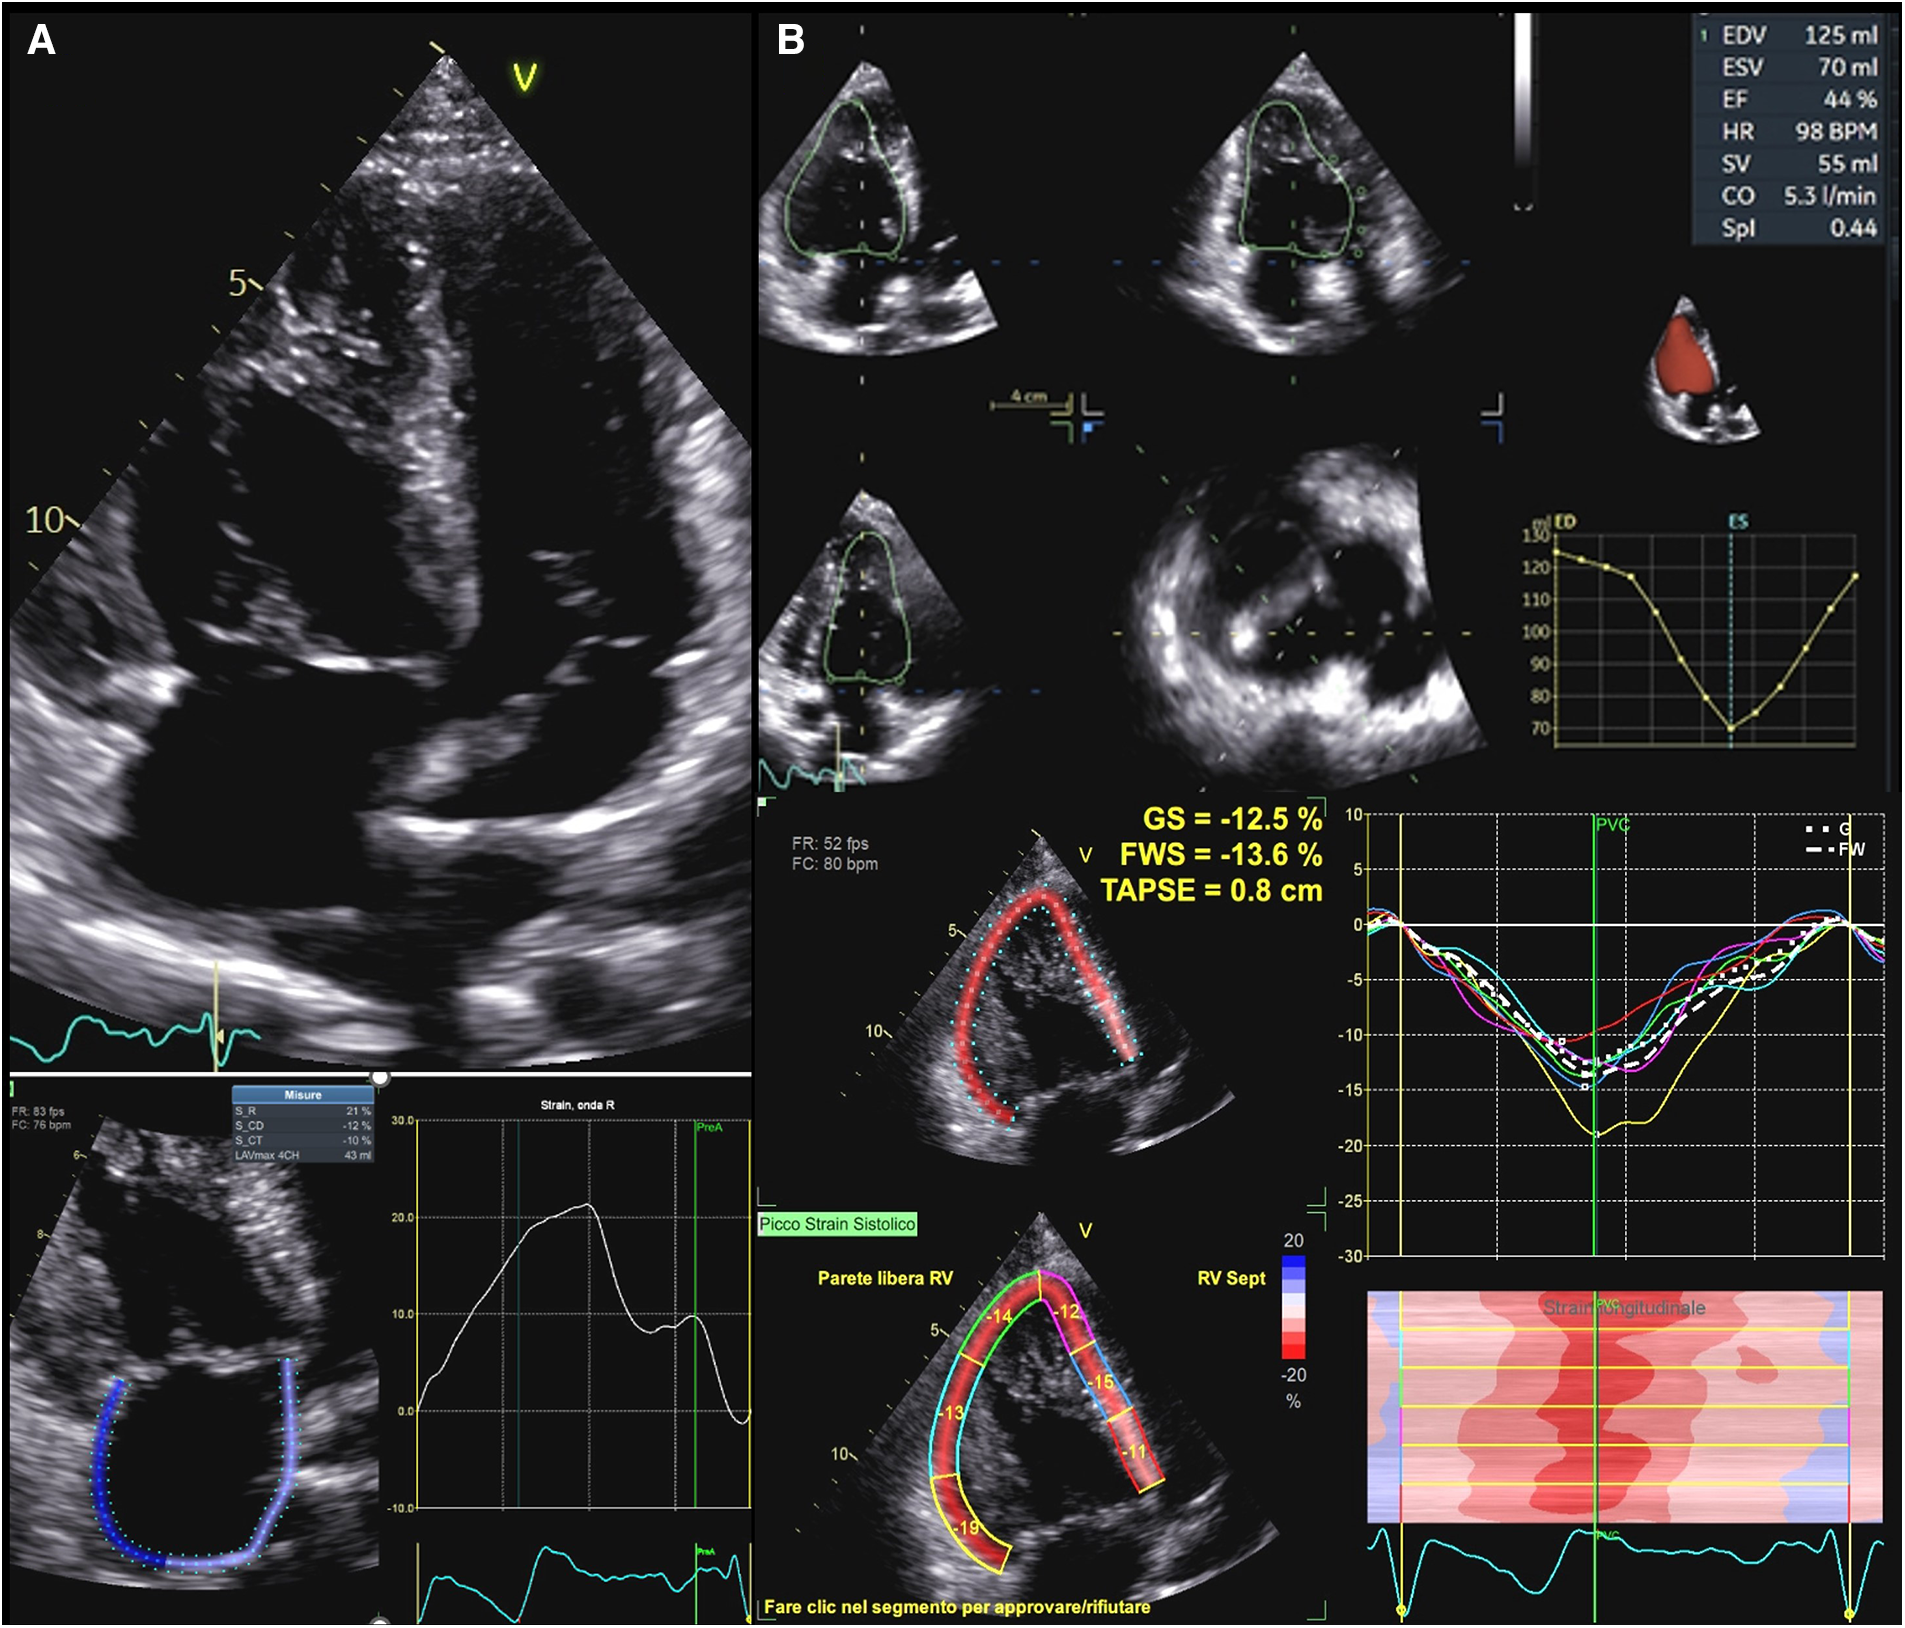

9.2 Echocardiographic assessment

Although its morphological features preclude the application of formulae based on geometrical assumptions, transthoracic echocardiography remains the main imaging modality to assess systemic right ventricular function (Figure 4). Many studies compared standard echocardiographic parameters, such as TAPSE and tissue doppler velocities of the tricuspid annulus, with EF calculated by CMR showing inconclusive results (109, 110). FAC, instead, seems to show a moderate correlation with ejection fraction from CMR (111). These indexes can therefore be more useful as controls for the same patients than as a precise quantification of myocardial function. Myocardial deformation imaging is a very attractive clinical tool for the assessment of RV systolic performance, since it provides incremental diagnostic and prognostic information over the traditional indices of RV function (112). In particular, STE allows to characterize contraction patterns separating longitudinal and circumferential components. Systemic right ventricles, in fact, seem to have a more circumferential pattern of contraction than sub-pulmonary ones. As shown by Wu et al., in D-TGA who underwent Senning or Mustard operation, longitudinal strain was reduced as well as in TOF patients if compared to healthy controls. However, circumferential strain was higher in sRVs than in TOF patients or in healthy controls and it correlated with ejection fraction at MR while longitudinal strain didn't (113). Moreover, circumferential strain seems to be the best echocardiographic predictor of exercise capacity in these patients (114). So, a possible compensatory increase in circumferential strain must always be considered when hypothesizing a dysfunction of the systemic right ventricle because longitudinal parameters might not be sensitive enough.

Figure 4

Functional assessment in systemic right ventricle physiologies. (A) Upper panel: apical 2D view in a patient with D-TGA after Senning operation. Lower panel: right atrial strain in the same patient. Atrial reservoir is impaired in this patient (21%). (B): Upper panel: sRV function as assessed by 3DE in a patient with ccTGA. Lower panel: GLS values in the same patient, which are impaired in all segments. D-TGA, D-transposition of great arteries; sRV, systemic right ventricle; 3DE, three-dimensional echocardiography; ccTGA, congenitally corrected transposition of great arteries.